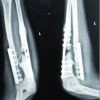

Her medical history revealed chronic kidney disease Stage IV and hypertension for which she was taking medication. Patient was examined for any other injury which may get masked because of these severe painful conditions. Radiological investigation revealed fracture neck of femur on right and intertrochanteric fracture on the left side (Fig. 1) and undisplaced fracture of lateral border of right scapula. Both lower limbs were immobilized with bilateral skin traction and for scapula fracture universal shoulder immobilizer was used. On investigation, she was found to be anemic with hemoglobin 5.7 gm/dl, her serum creatinine level was 4.83 mg/dl, and serum potassium was 2.8 meq/l. General physician, nephrologist, and anaesthesiologist were involved to optimize the medical condition of the patient as she needed major surgery. She was an active lady and our goal was to bring her to pre-injury level as early as possible. Dynamic hip screw fixation has stood the test of time for fixation of stable intertrochanteric fracture. In elderly patient, a prosthetic replacement is adequate for fracture neck of femur but at the age of 41 years it was reasonable to plan preserving the femoral head. The presence of this combination of injury in a comorbid patient and trying to preserve the femoral head presented an additional challenge in attempted osteosynthesis.

We planned dynamic hip screw for the intertrochanteric fracture and multiple cannulated cancellous screws to stabilize fracture neck of femur in the same sitting. The patient and relatives were prognosticated about the per-operative, post-operative, early, and late complications. In the operation theater with the patient on traction table, we first stabilized the intertrochanteric fracture with dynamic hip screw on the left side. After attempting closed reduction of the displaced femoral neck fracture on the right side, under image intensification, and having achieved it, it was fixed with three 6.5 mm cannulated cancellous screws, one of them as derotation screw. The per-operative period was uneventful. For next 48 h, she was kept in high dependency unit for monitoring after which she was shifted to the general orthopedic ward. Check X-ray taken on 2nd post-operative day was acceptable (Fig. 2, 3, 4). The same day 1st change of dressing was done. In bed physiotherapy was started with leg hanging and quadriceps exercise. Right shoulder remained immobilized. Patient was discharged with advice to attend OPD for stitch removal on 14th post-operative day. At stitch removal, her surgical wounds were found to be healthy. Patient was advised to carry on physiotherapy and non-weight bearing and was asked to follow-up after 1 month.